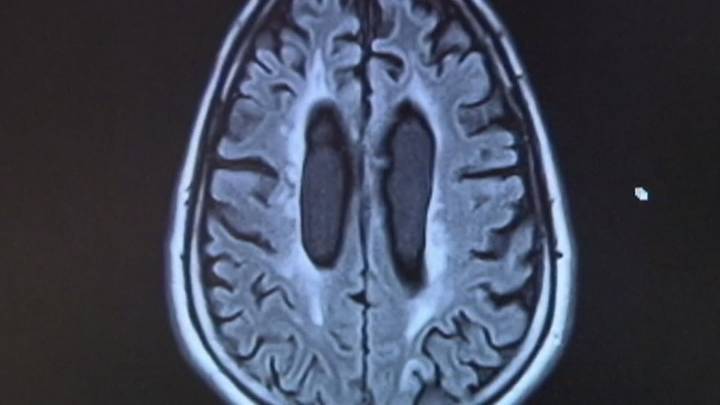

La , si es aprobada por los votantes, asignaría $3,000 millones del ingreso general del estado para establecer el Instituto de Prevención e Investigación de la Demencia de Texas. Los fondos apoyarían al instituto durante la próxima década, con la misión de avanzar en el tratamiento, prevención e investigación de enfermedades relacionadas con la demencia.

Según la Texas ocupa actualmente el tercer lugar en la nación en casos de demencia y el segundo en muertes relacionadas con la enfermedad. Más de 450,000 texanos mayores viven con la enfermedad de Alzheim